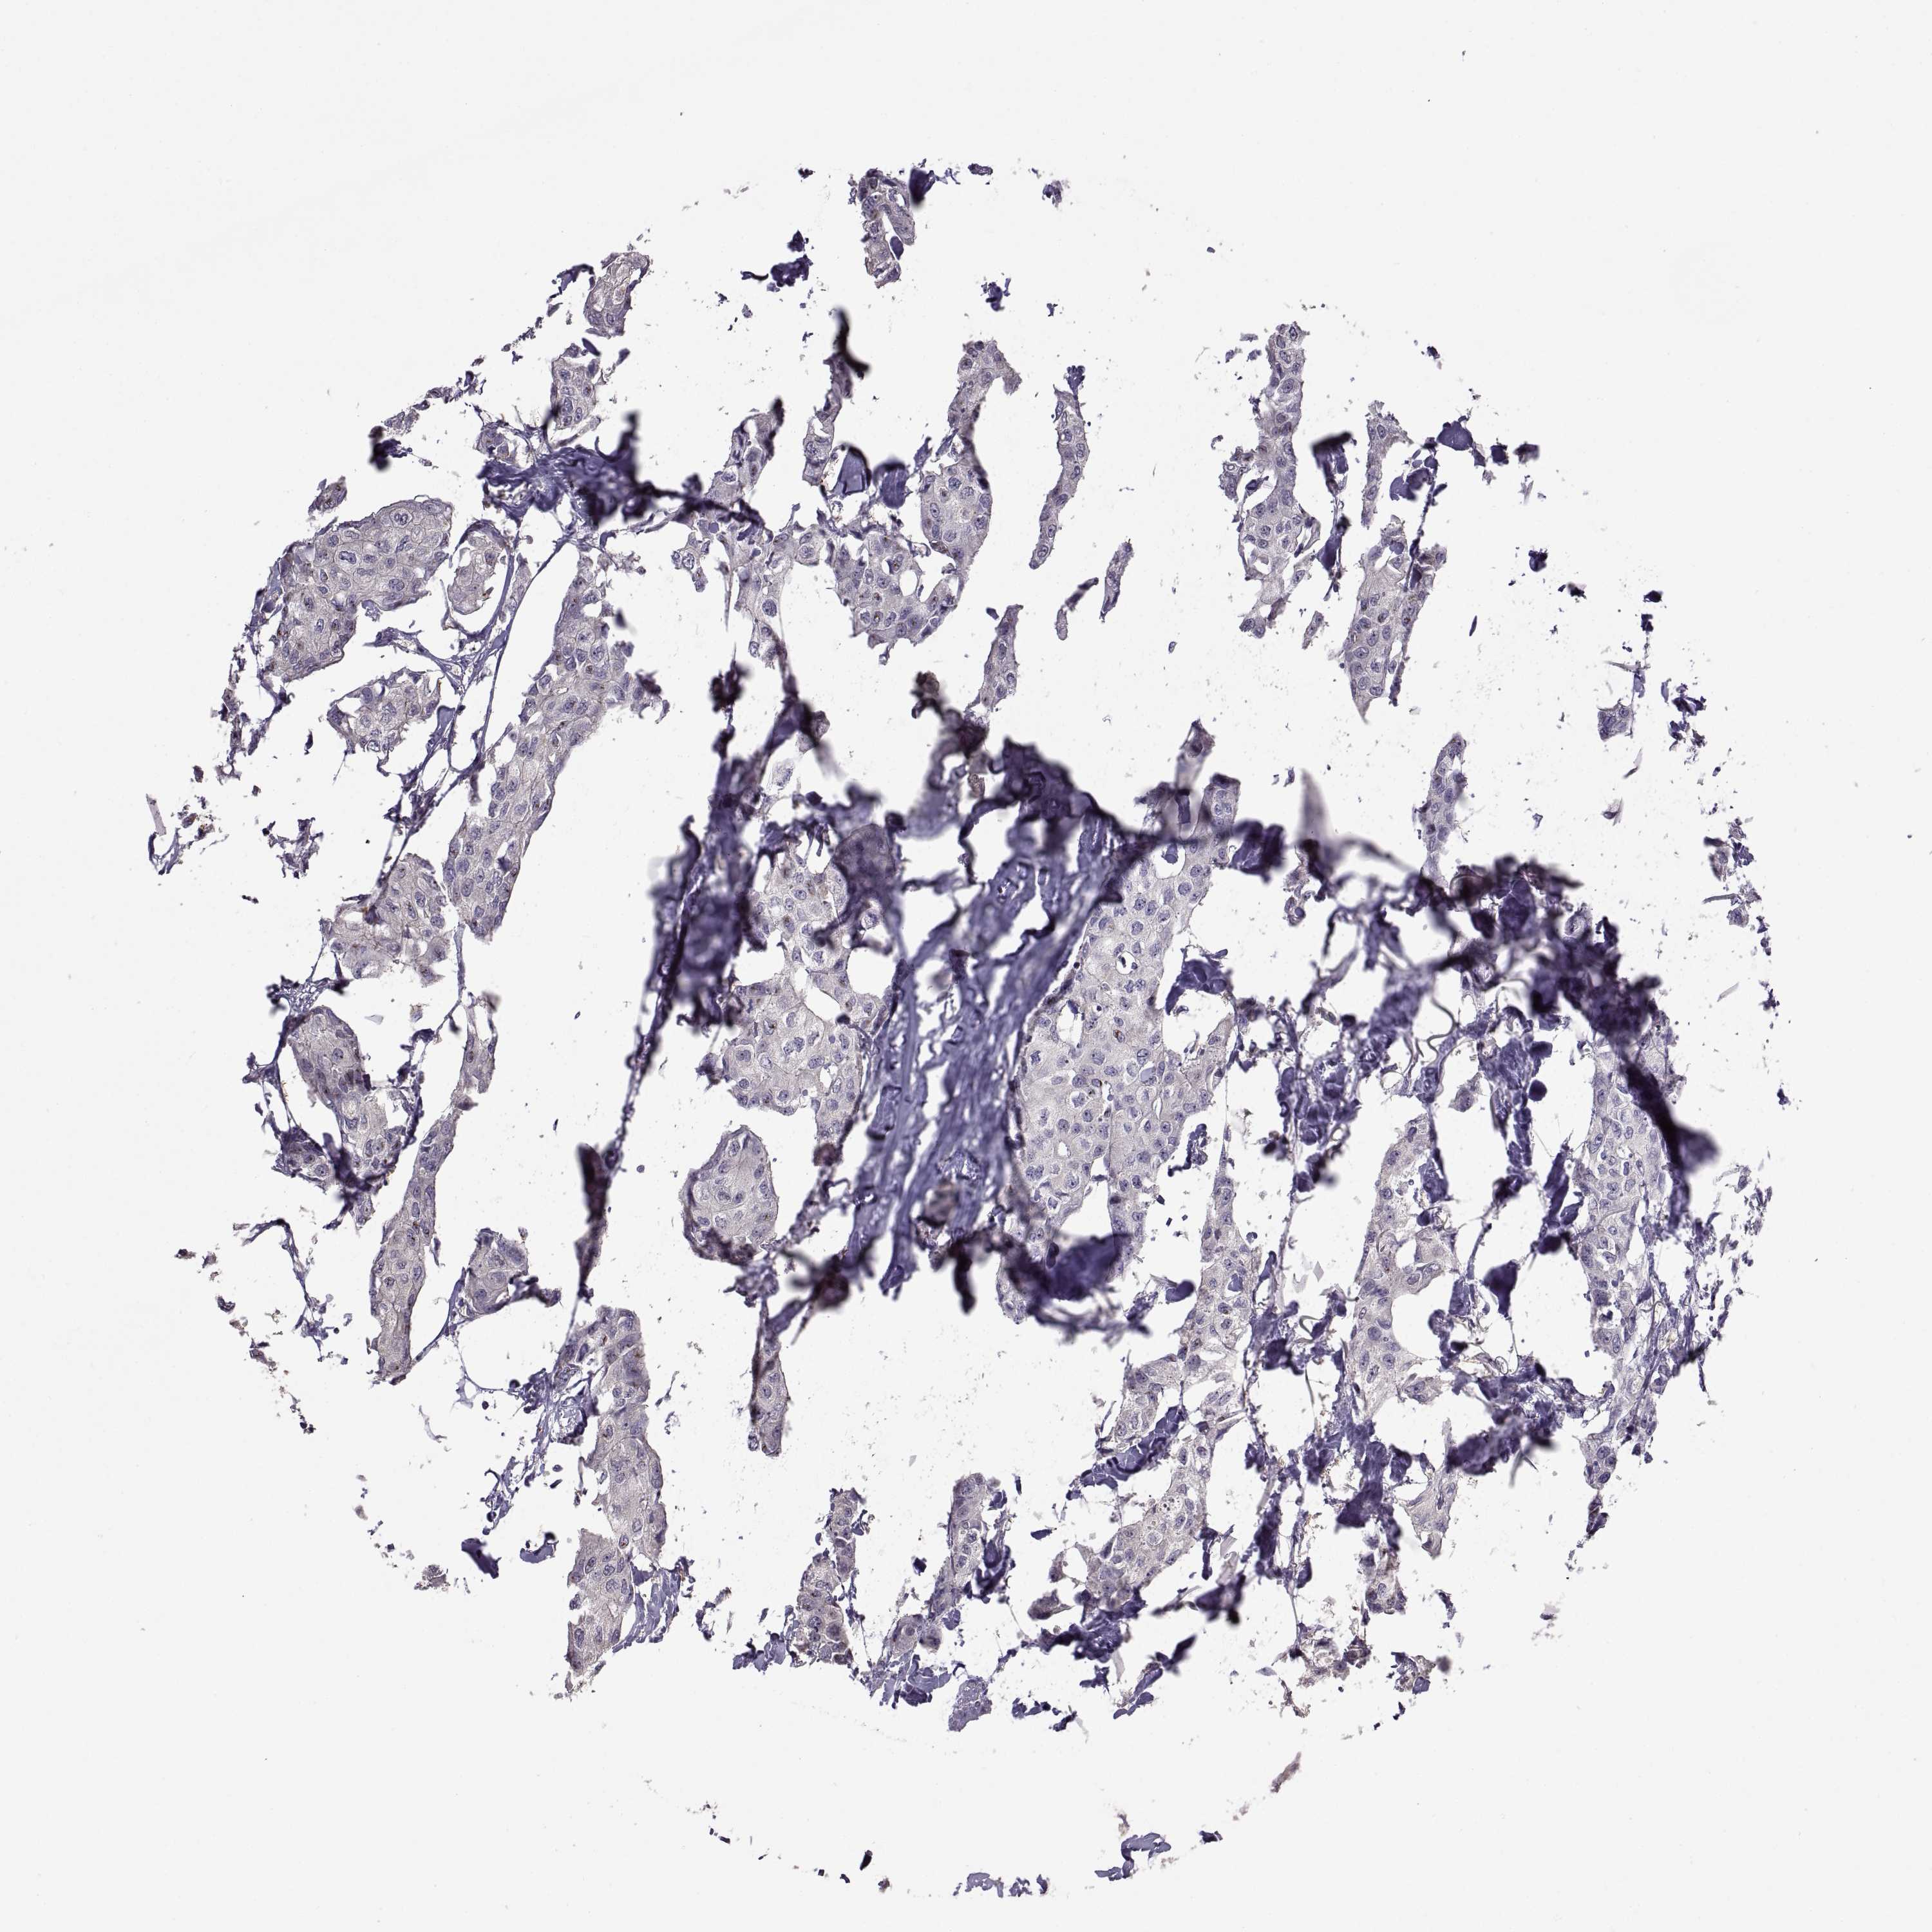

CANCER BREAST CANCER Show tissue menu

BRCA TCGA BRCA VALIDATION PROTEIN EXPRESSION

Breast cancer

Human cancer